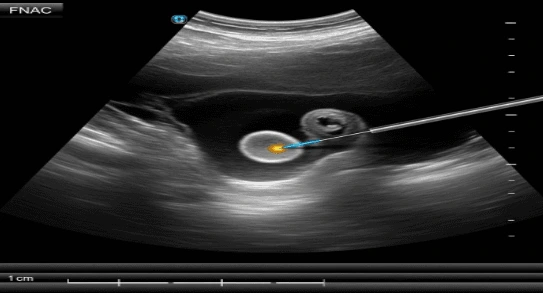

Under ultrasound guidance, real-time imaging allows the physician to guide the needle directly into the target in the nodule or the lymph nodes, increasing the quality of the procedure and alleviating the possibility of sampling the wrong spot. FNAC is a rather swift technique, although the entire visit may involve a little preparation and observation

2) Ultrasound-Guided FNAC This is preferred when:

- the nodule is small

- it is deep or not clearly felt

- precise sampling is important (like thyroid nodules)

- the lesion has mixed solid/cystic areas and needs targeted sampling Ultrasound guidance improves accuracy and lowers the chance of “insufficient sample,” which is a common reason for repeat FNAC.